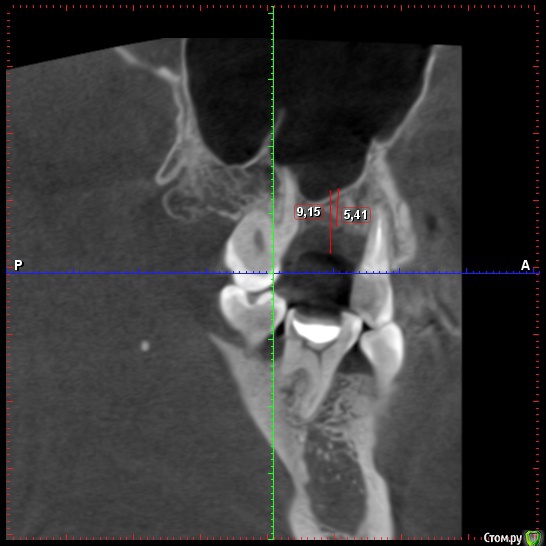

Eddie Опубликовано 8 октября, 2018 Поделиться Опубликовано 8 октября, 2018 Нужен синус. Менее плотная ткань- это слизистая. 2 Ссылка на комментарий

АнтонТЛТ Опубликовано 8 октября, 2018 Поделиться Опубликовано 8 октября, 2018 5.41мм правильный замер. Зубы могут быть устойчивыми и при меньшем объеме костной ткани вокруг. 2 Ссылка на комментарий

zubovolok Опубликовано 8 октября, 2018 Автор Поделиться Опубликовано 8 октября, 2018 5.41мм правильный замер. Зубы могут быть устойчивыми и при меньшем объеме костной ткани вокруг.Антон, можно будет закрытым обойтись? (имплант 8мм имплантиум) Ссылка на комментарий

АнтонТЛТ Опубликовано 8 октября, 2018 Поделиться Опубликовано 8 октября, 2018 Антон, можно будет закрытым обойтись? (имплант 8мм имплантиум)Если опыт есть, то можно. Если нет, то открытый будет более предсказуемым. Ссылка на комментарий

Nazim_NV86 Опубликовано 8 октября, 2018 Поделиться Опубликовано 8 октября, 2018 нет не достиг, я интересуюсьДля открытого довольно таки хороший и удобный случайю . Согласен с Антоном. 2 Ссылка на комментарий